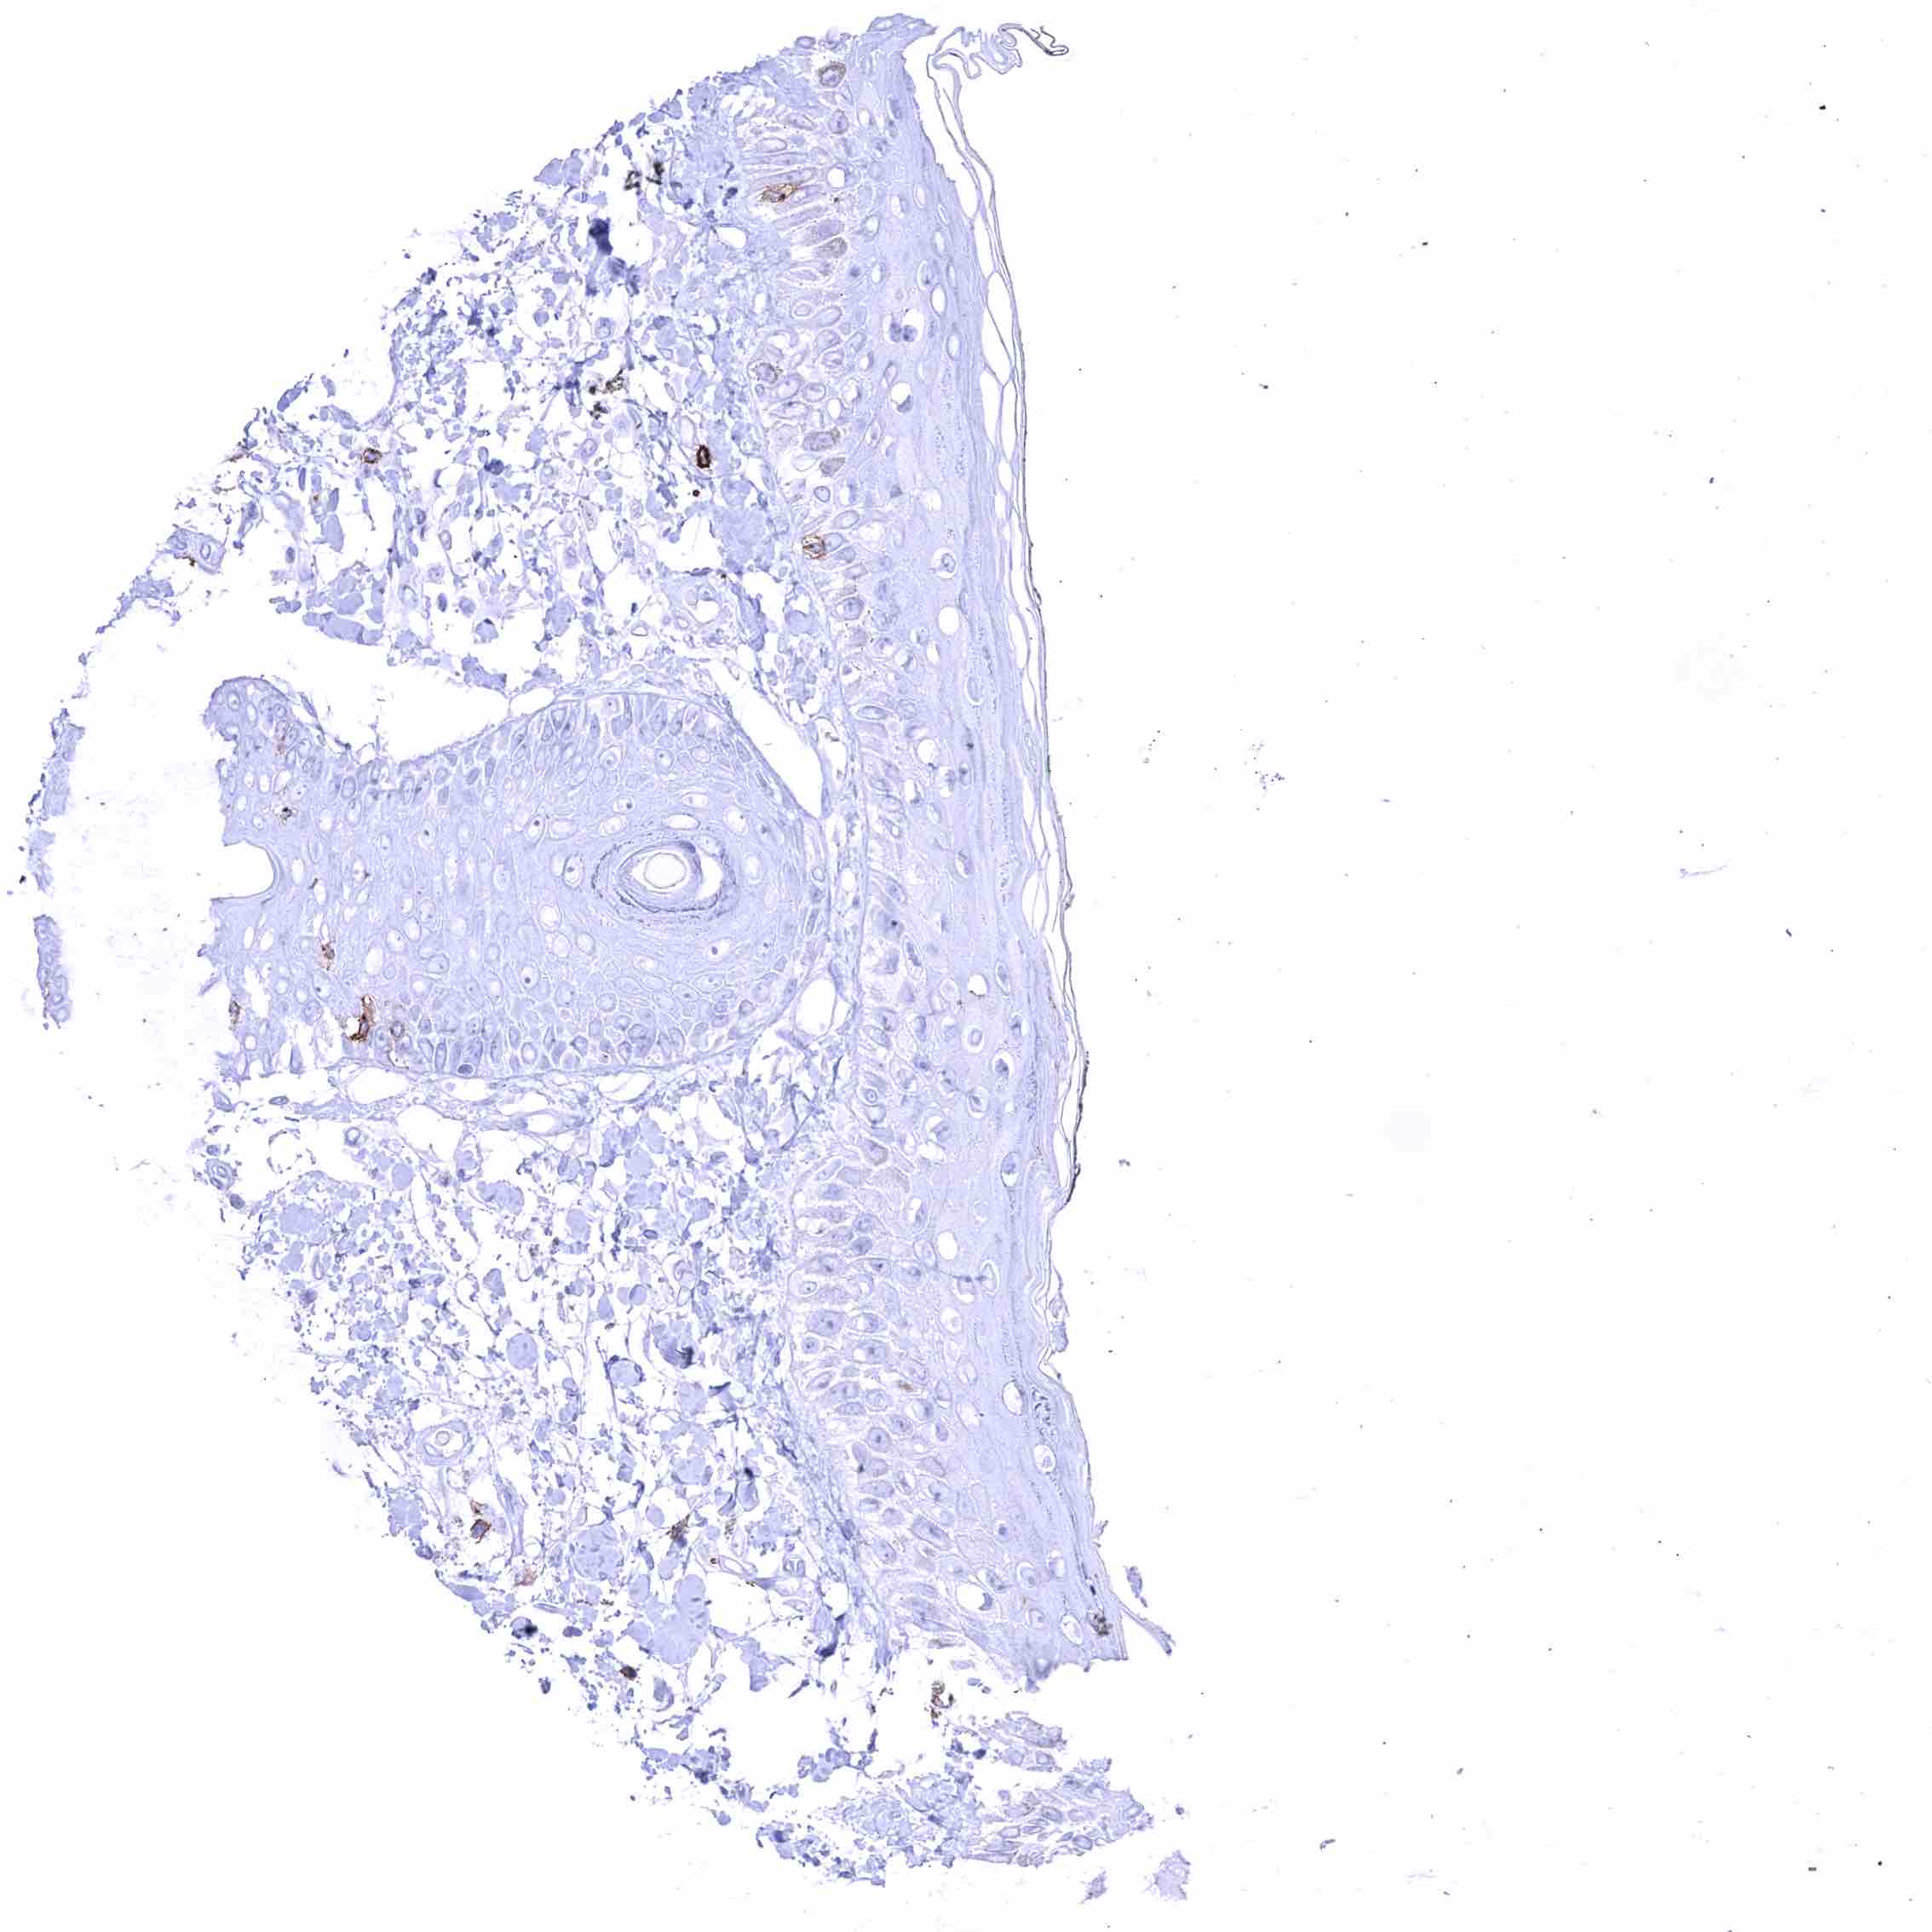

Positive control = Appendix: A distinct membranous CD70 staining should be seen in a subset of inflammatory cells (especially interfollicular).

Negative control = Appendix: CD70 staining should be absent in epithelial cells.

| Appendix | Distinct CD70 positivity of a fraction of lymphocytic cells, predominantly interfollicular. Epithelial cells are CD70 negative. | |

| Tonsil | Membranous CD70 staining of variable intensity in subsets of inflammatory cells (mostly lymphocytes). Most CD70 positive cells are interfollicular. Squamous epithelium remains CD70 negative. | |